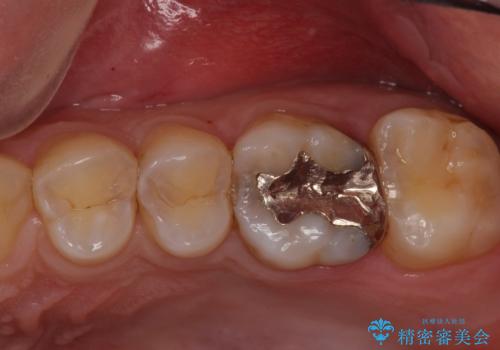

歯茎が腫れた。ジルコニアクラウンやりかえ。

- メンテナンスで来院された患者様です。

歯茎が腫れたとの事で歯の神経が失活していたので精密根管治療を行い、ジルコニアクラウンで治療を行いました。

- ジルコニアクラウンスタンダード・仮歯 12.1万円 精密根管治療(イニシャルトリートメント)・ファイバーコア 13.2万円費用は治療当時の料金となります

神経が失活しているので痛みは感じにくいですがこのまま放置をしてしまうと骨が溶けたり痛みが出たりします。